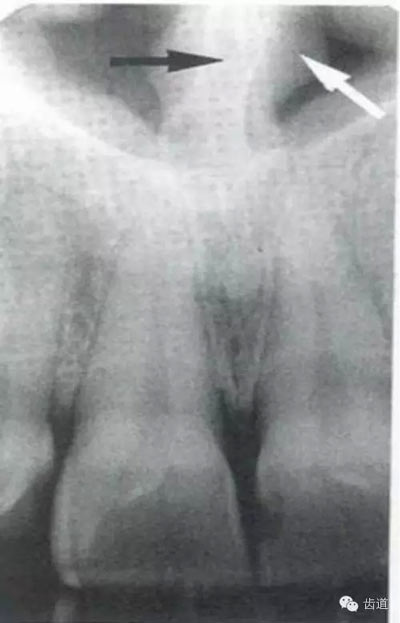

牙頸部Burnout征象:有時因投照技術(shù)問題而造成牙頸部近中或遠(yuǎn)中呈低密度影像,位于牙釉質(zhì)和牙槽嵴頂之間。